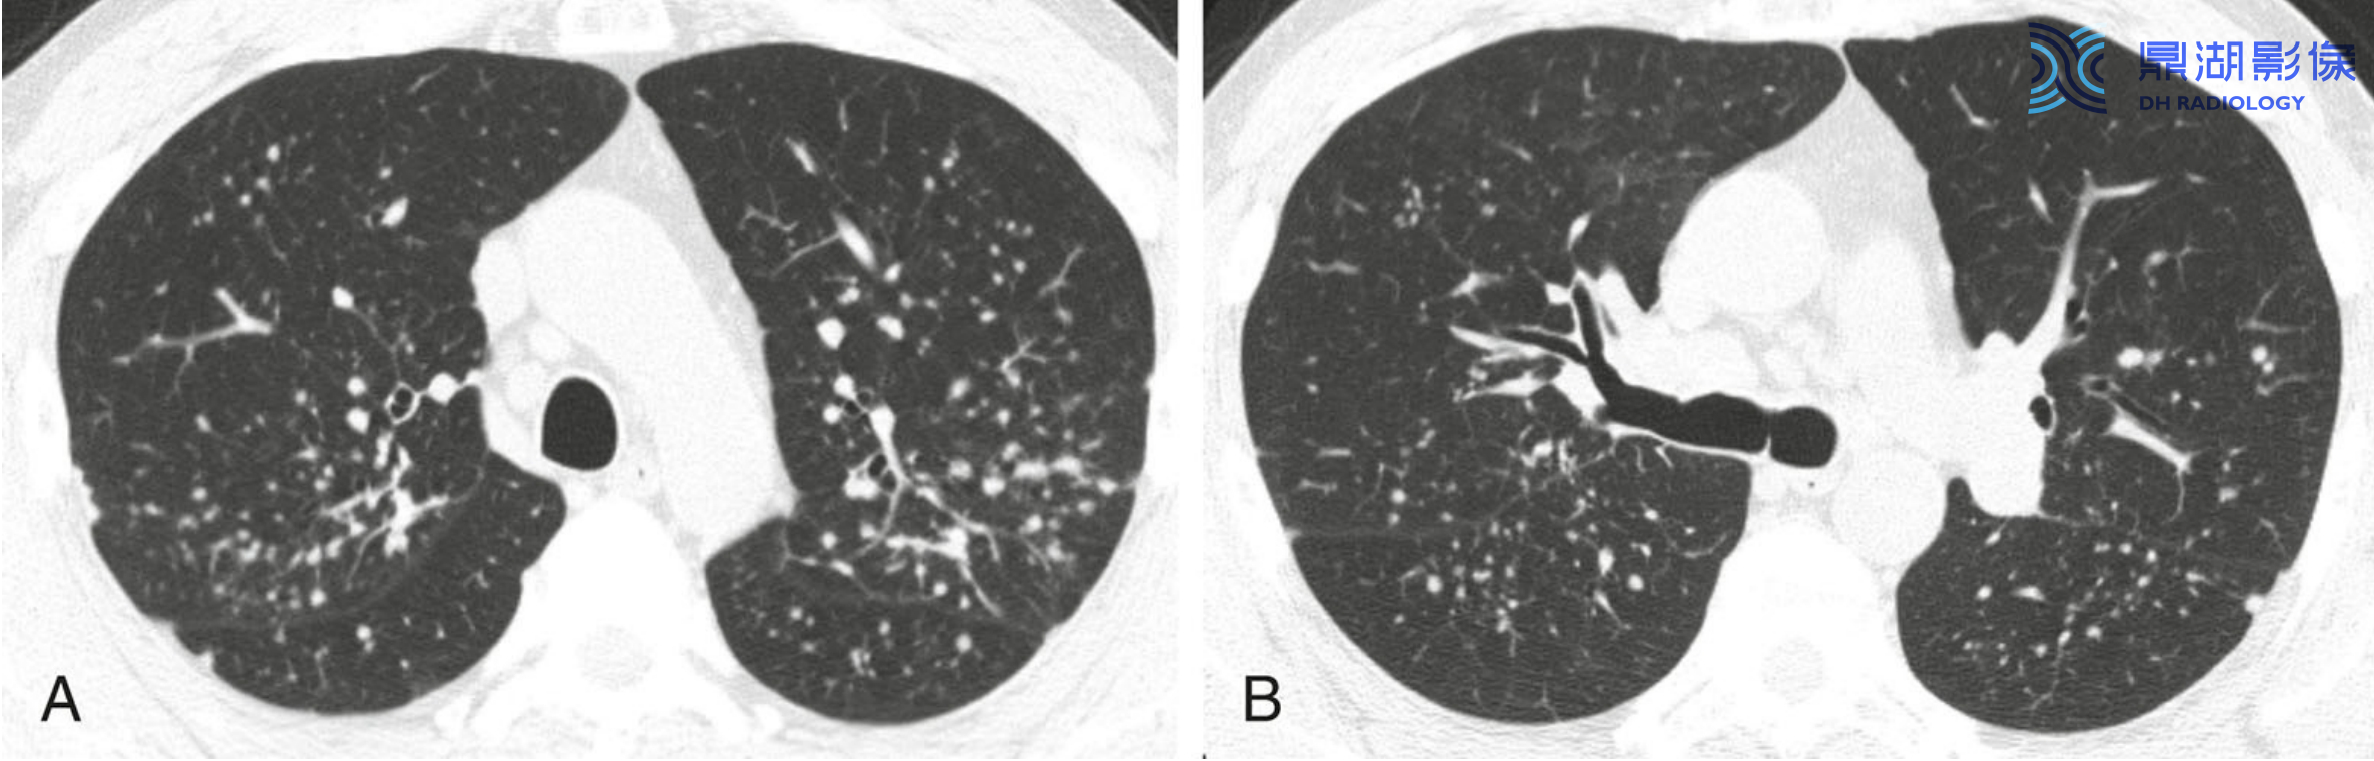

0bf39ca4c88272289348361260f5dc2c.png

肺泡型结节病及“星系征" 的典型表现。A和B支气管血管周围可见融合的肉芽肿所形成的肺门旁团块样实变。实变内可见支气管充气征。大片团块影周围分布的小结节即卫星结节,大团块影与其周围环绕的小结节合称为“ 星系征”

09bcb3e8a2a27fe3ab06e3875d3923b3.png

结节病伴实变。结节病可见实变(黄箭),伴有支气管血管周围(红箭)和胸膜下(蓝箭)散在分布的多发结节。实变代表融合的肉芽肿。